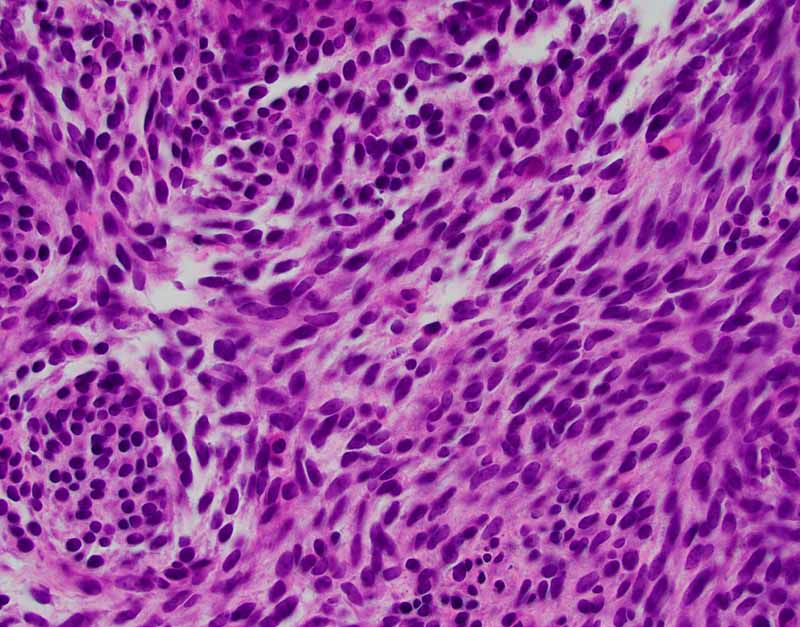

TLE-1

Cytology of the Case: The background is dominated by a substantial amount of mucoid material (Panel A) and admixed with these materials are small clusters of neoplastic cells. Some delicate blood vessels are also present (Panel B). A small number of tumor cells are adhered to these blood vessels but there is a lack of genuine papillary arrangement. The cells are epithelioid and contains a moderate amount of cytoplasm (Panel B, C, D, E, and F) that are finely vacuolated (Panel D and F) in some of them. The neoplastic cells are rather adhesive to each other. The nuclei are hyperchromatic and without pseudonuclear inclusion in most of them. There is no prominent nucleoli A minute amount of tissue is present in the cell block (Panel G). There is definitive gland formation. Some spindle neoplastic cells (S in Panel G) are also present next to the glandular structure. The nuclear features of these cells are identical to that of the glandular cells.

Immunohistochemistry: The tumor cells are positivefor TLE-1 (nuclear staining) (Panel H) and cytokeratin 7 but negative for GCDFP-1.

Cytogenetics: FISH was performed and no rearrangement of SS18 was demonstrated.

Histology of the Case: The lesion is an encapsulated neoplasm a glandular component and a myxoid component (Panel I and J). The two comonents are well demarcated without transition from one into another. Although the myxoid component (Panel K and L) is not present in the cell block of the FNA, the myxoid substance of the FNA comes from this myxoid component. The glandular component (Panel M, N, O, P) is composed of well formed glands with PAS positive mucoid content in the lumen (Panel Q). In between the well formed glands are spindle cells with nuclear features identical to that of the glands (S in Panel N). This component is present in the cell block of the FNA and is the major clue for the diagnosis.

Immunohistochemistry: The tumor cells are also positive for cytokertin 7 and TLE-1. Positive immunoreactivity for cytokeratin 7 (Panel R) and EMA are also present extensively in the epithelial cells. The spindle cell component are positive ofr EGFR and CD99. Both epithelial and spindle cell components show positive nuclear immunoreactivity for TLE-1 (Panel S).